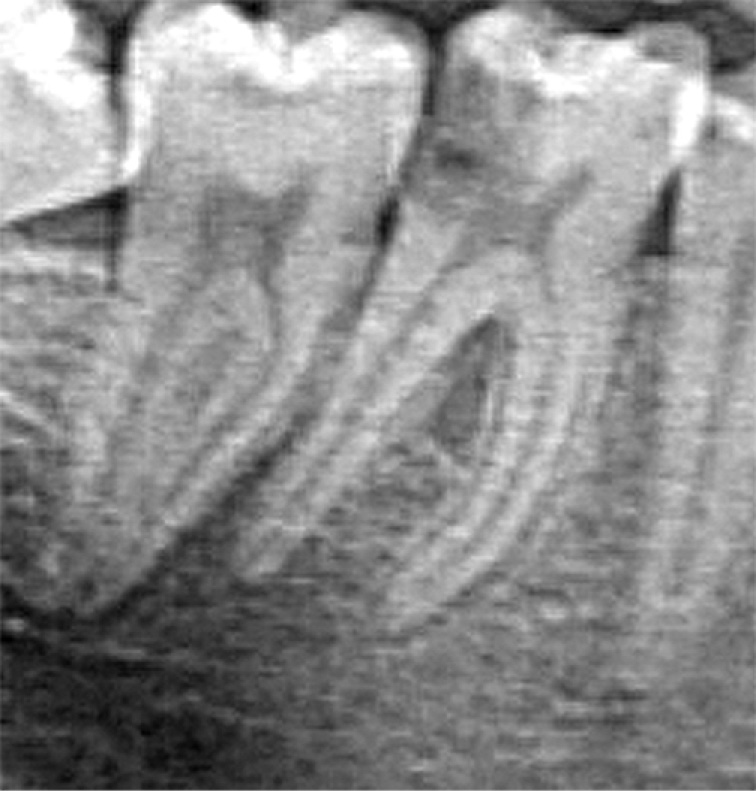

One illustrative case involved a 47-year-old patient who had recovered from COVID-19 less than a year prior to the dental appointment. Candida elements were detected in the specimen, and the diagnosis of chronic gangrenous pulpitis of tooth 46 (FDI/ISO notation) was established. A periapical radiograph of tooth 46 (see Fig. 1) and a microphotograph of the canal contents (see Fig. 2) are provided.

Fig. 1. Intraoral periapical radiograph of tooth 46.